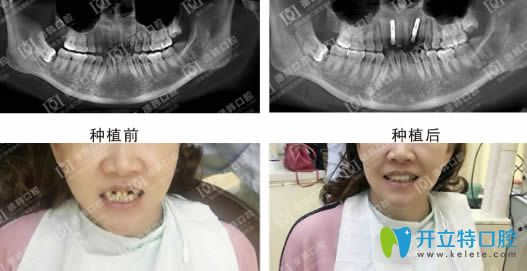

說一千,道一萬,武漢德韓種植牙到底怎么樣,不如效果展示來的實在:

德韓口腔種植牙效果前后對比圖

武漢德韓口腔憑借先進的臨床影像采集技術、口內模型掃描取像及團隊醫(yī)師會診等一體化流程,結合CAD/CAM技術,實現種植體的精確植入,有效保護神經和血管,保障您的安全與長期使用效果?,F在,武漢德韓口腔為您提供進口種植牙服務,僅需3980元,并由種植博士親自診療,歡迎前來咨詢體驗。